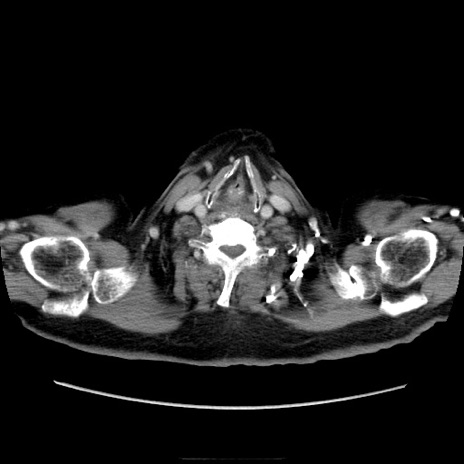

症例21(横断像)

【症例】70歳代男性

【主訴】腹痛

【現病歴】肝硬変・肝細胞癌にてかかりつけの方。約9時間前に食後より腹痛出現。症状が徐々に増悪し、嘔吐出現したため来院。

【既往歴】肝硬変、肝細胞癌(RFA、TACE後)

【身体所見】意識清明、表情苦悶様、BT 36℃、BP 129/78mmHg、P 88bpm、SpO2 97%(RA)、右上腹部から心窩部にかけて圧痛あり、反跳痛なし、筋性防御あり。

【データ】WBC 5800、CRP 0.16